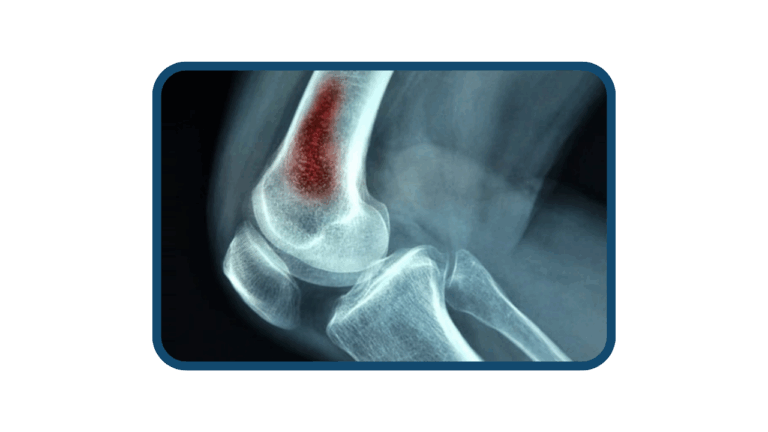

La osteomielitis es una de las infecciones más comunes que suelen llegar a Clínica Arthrosalud. Es una condición que puede causar dolor, inflamación y daño óseo. Por lo que requiere de intervención especializada por parte de nuestros traumatólogos, con el fin de eliminar la infección y preservar la función del hueso con una reconstrucción ósea.